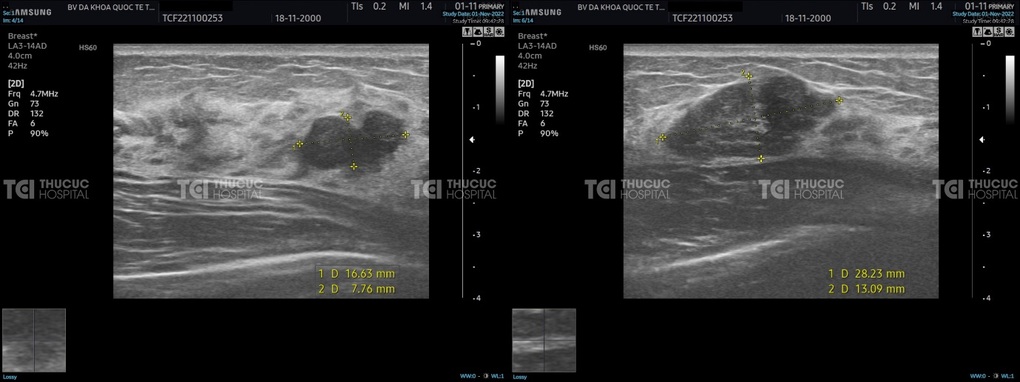

ThS.BS Trần Đức Ngọc, khoa Can thiệp và Chẩn đoán hình ảnh - Bệnh viện Đa khoa Quốc tế (ĐKQT) Thu Cúc TCI cho biết, bệnh nhân L.T.T (22 tuổi - Hoàng Mai, Hà Nội) đến thăm khám trong tình trạng ngực sưng đau bất thường, chạm vào thấy rõ các khối di chuyển. Sau các bước kiểm tra lâm sàng và cận lâm sàng, chị T. được chẩn đoán đa nhân tuyến vú hai bên với tất cả 15 khối u ở 2 bên ngực (7 khối u ở vú phải và 8 khối u vú trái). Trong đó, u lớn nhất có kích thước 3,1 cm, nhiều nhân kích thước từ 1-2cm, vị trí 2h tại vú trái còn có nhiều nhân tạo thành đám.

Kết quả chụp nhũ ảnh cũng cho thấy bệnh nhân có u tuyến vú BI-RADS 3 (hay nhân xơ tuyến vú BI-RADS 3), đồng nghĩa khả năng u là lành tính nhưng cũng tiềm ẩn nguy cơ u ác tính dù chỉ 0,8%.

Trường hợp bệnh nhân L.T.T có tổn thương tuyến vú lan rộng khi mới 22 tuổi, trong đó có khối u kích thước lớn, sau khi cân nhắc các phương pháp điều trị, các bác sĩ TCI đã chỉ định sinh thiết u vú dưới hướng dẫn của siêu âm và lực hút chân không để loại 15 khối u trên ngực của người bệnh.

Sinh thiết u vú dưới hướng dẫn của siêu âm và lực hút chân không tại Thu Cúc TCI (Ảnh: TCI).